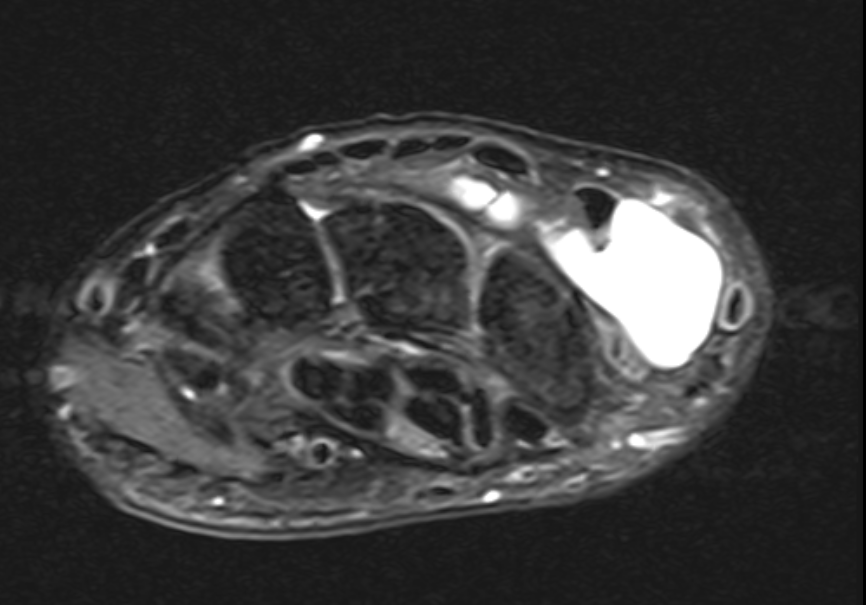

Dorsal ganglion

Dorsal ganglion arising from scapholunate joint

Dorsal ganglion arising from scapho-lunate joint